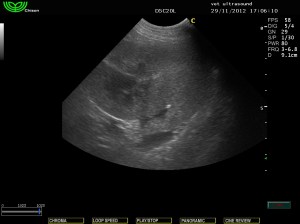

Στην υπερηχοτομογραφική εξέταση της κοιλίας βρέθηκε αύξηση της ηχογένειας της φλοιώδους μοίρας των νεφρών.

(ίδια ηχογένεια με το παρέγχυμα του σπλήνα)